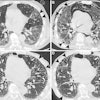

Two drug-sensitive cases (above) and two drug-resistant cases (below). Each column shows one x-ray image and one CT slice. Images courtesy of Vasiliy Kovalev.Feature analysis